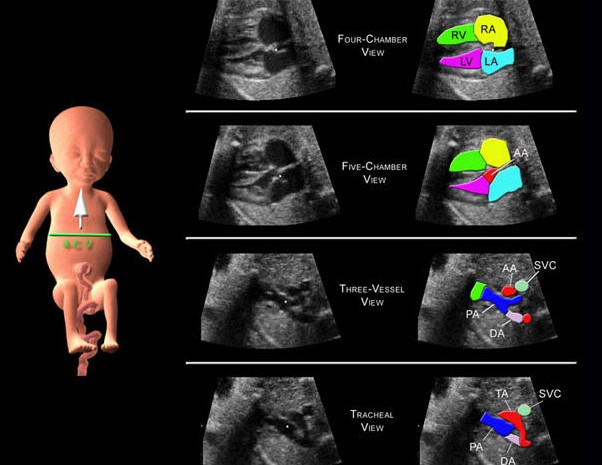

O QUE É ECOCARDIO FETAL? É um exame de ultrassom que permite avaliar o...